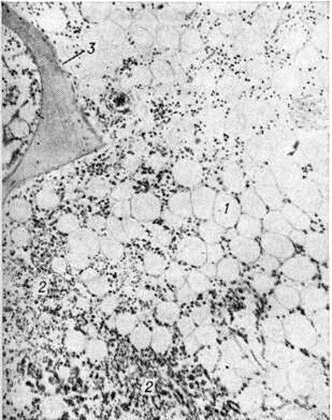

При остром мегакариобластном лейкозе в костном мозге выявляется большое количество атипичных мегакариоцитов и мегакариобластов, которые диффузно рассеяны в ткани, а местами образуют скопления (рисунок 4). Такие же клетки в значительном количестве содержатся в ткани и синусах селезёнки, лимфатических, узлов, просветах мелких сосудов печени, лёгких и других органов.